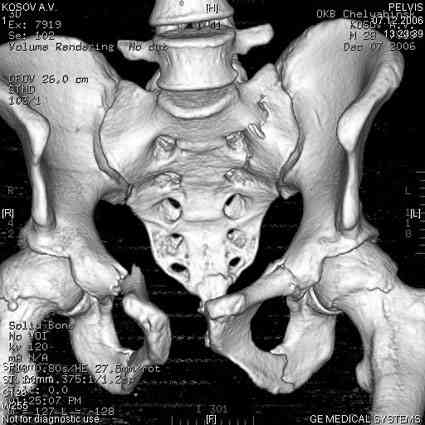

18.12. - отдельное спасибо еще раз А.В.Рункову- больного оперировали (А.В.Рунков) - произведен остеосинтез аппаратом - фиксация за крылья, два стержня в лонные кости и репозиция (почти полная) снимки будут чуть позже.

Дренировали отслойки на бедрах с их санацией. В правой ягодичной области сформировалась зона некроза. Больной "подвешен" за аппарат.